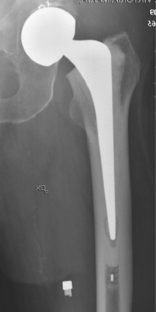

Unipolar versus bipolar Exeter hip hemiarthroplasty: a prospective cohort study on 830 consecutive hips in patients with femoral neck fractures

In this study we analysed the reoperation and the dislocation rates for Exeter HAs in patients with a displaced femoral neck fracture, comparing the unipolar and bipolar prosthetic designs. Additionally, we compared the outcome for HAs performed as a primary intervention with those performed secondary to failed internal fixation.

We studied 830 consecutive Exeter HAs (427 unipolar and 403 bipolar) performed either as a primary operation for a displaced fracture of the femoral neck or as a secondary procedure after failed internal fixation of a fracture of the femoral neck. Cox regression analyses were performed to evaluate factors associated with reoperation and prosthetic dislocation. Age, gender, the surgeon’s experience, indication for surgery (primary or secondary) and type of HA (unipolar or bipolar) were tested as independent variables in the model.

The prosthetic design (uni- or bipolar) had no influence on the risk for reoperation or dislocation, nor had the age, gender or the surgeon’s experience. The secondary HAs were associated with a significantly increased risk for reoperation (HR 2.6, CI 1.5–4.5) or dislocation (HR 3.3, CI 1.4–7.3) compared to the primary HAs. We found no difference in the risk for reoperation or dislocation when comparing Exeter unipolar and bipolar HAs, but special attention is called for to reduce the risk of prosthesis dislocation and reoperation after a secondary HA.

Fig. 1